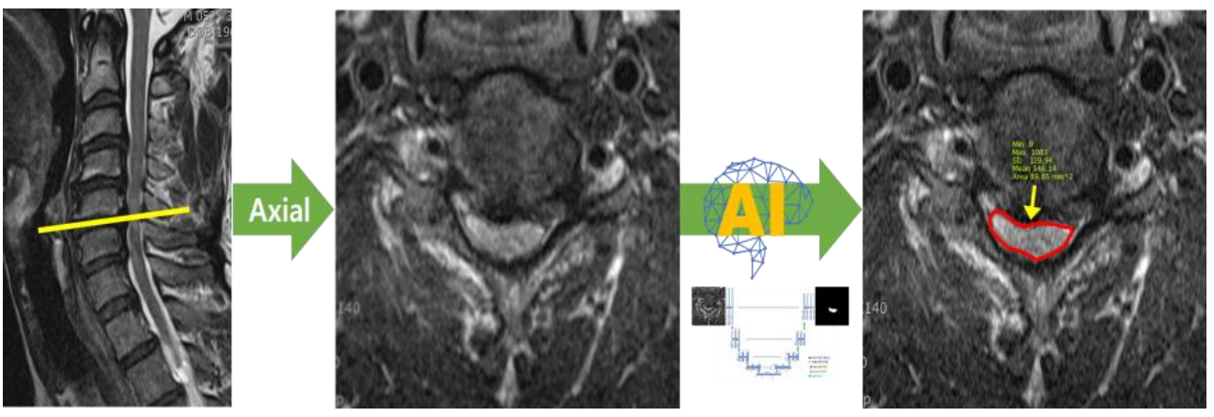

3. T2 Axial에서의 척수 영역 분할 및 면적 측정 모델

- 모델 학습

- 바이오 의료 영상 분야에서 분할을 목적으로 만들어진 모델을 사용하여 학습을 진행.

- Erode 및 Dilate, Median Blur를 이용해 이미지 후처리. Noise 및 Hole 제거

[T2 MRI에서 척수 영역 분할 모델 개요]

- 척추 면적 측정

- Dicom Header의 Pixel Spacing 정보를 통해 AI 결과에 대한 면적(mm2) 측정

[척추 영역 면적 측정]